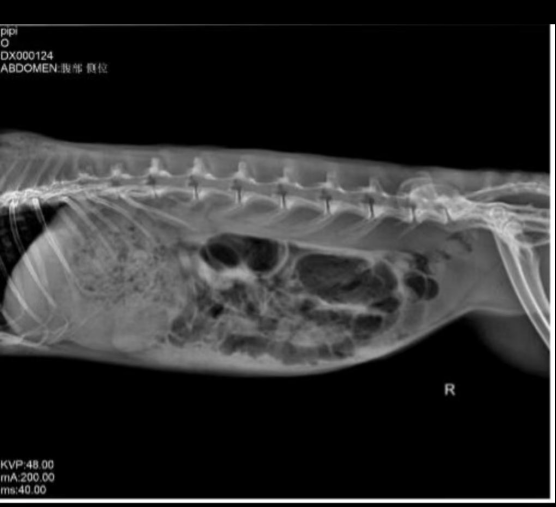

X-ray imaging revealed severe cecal bloating and food accumulation in the stomach. We advised the owner to be cautious when reviewing the images, as they could be unsettling.